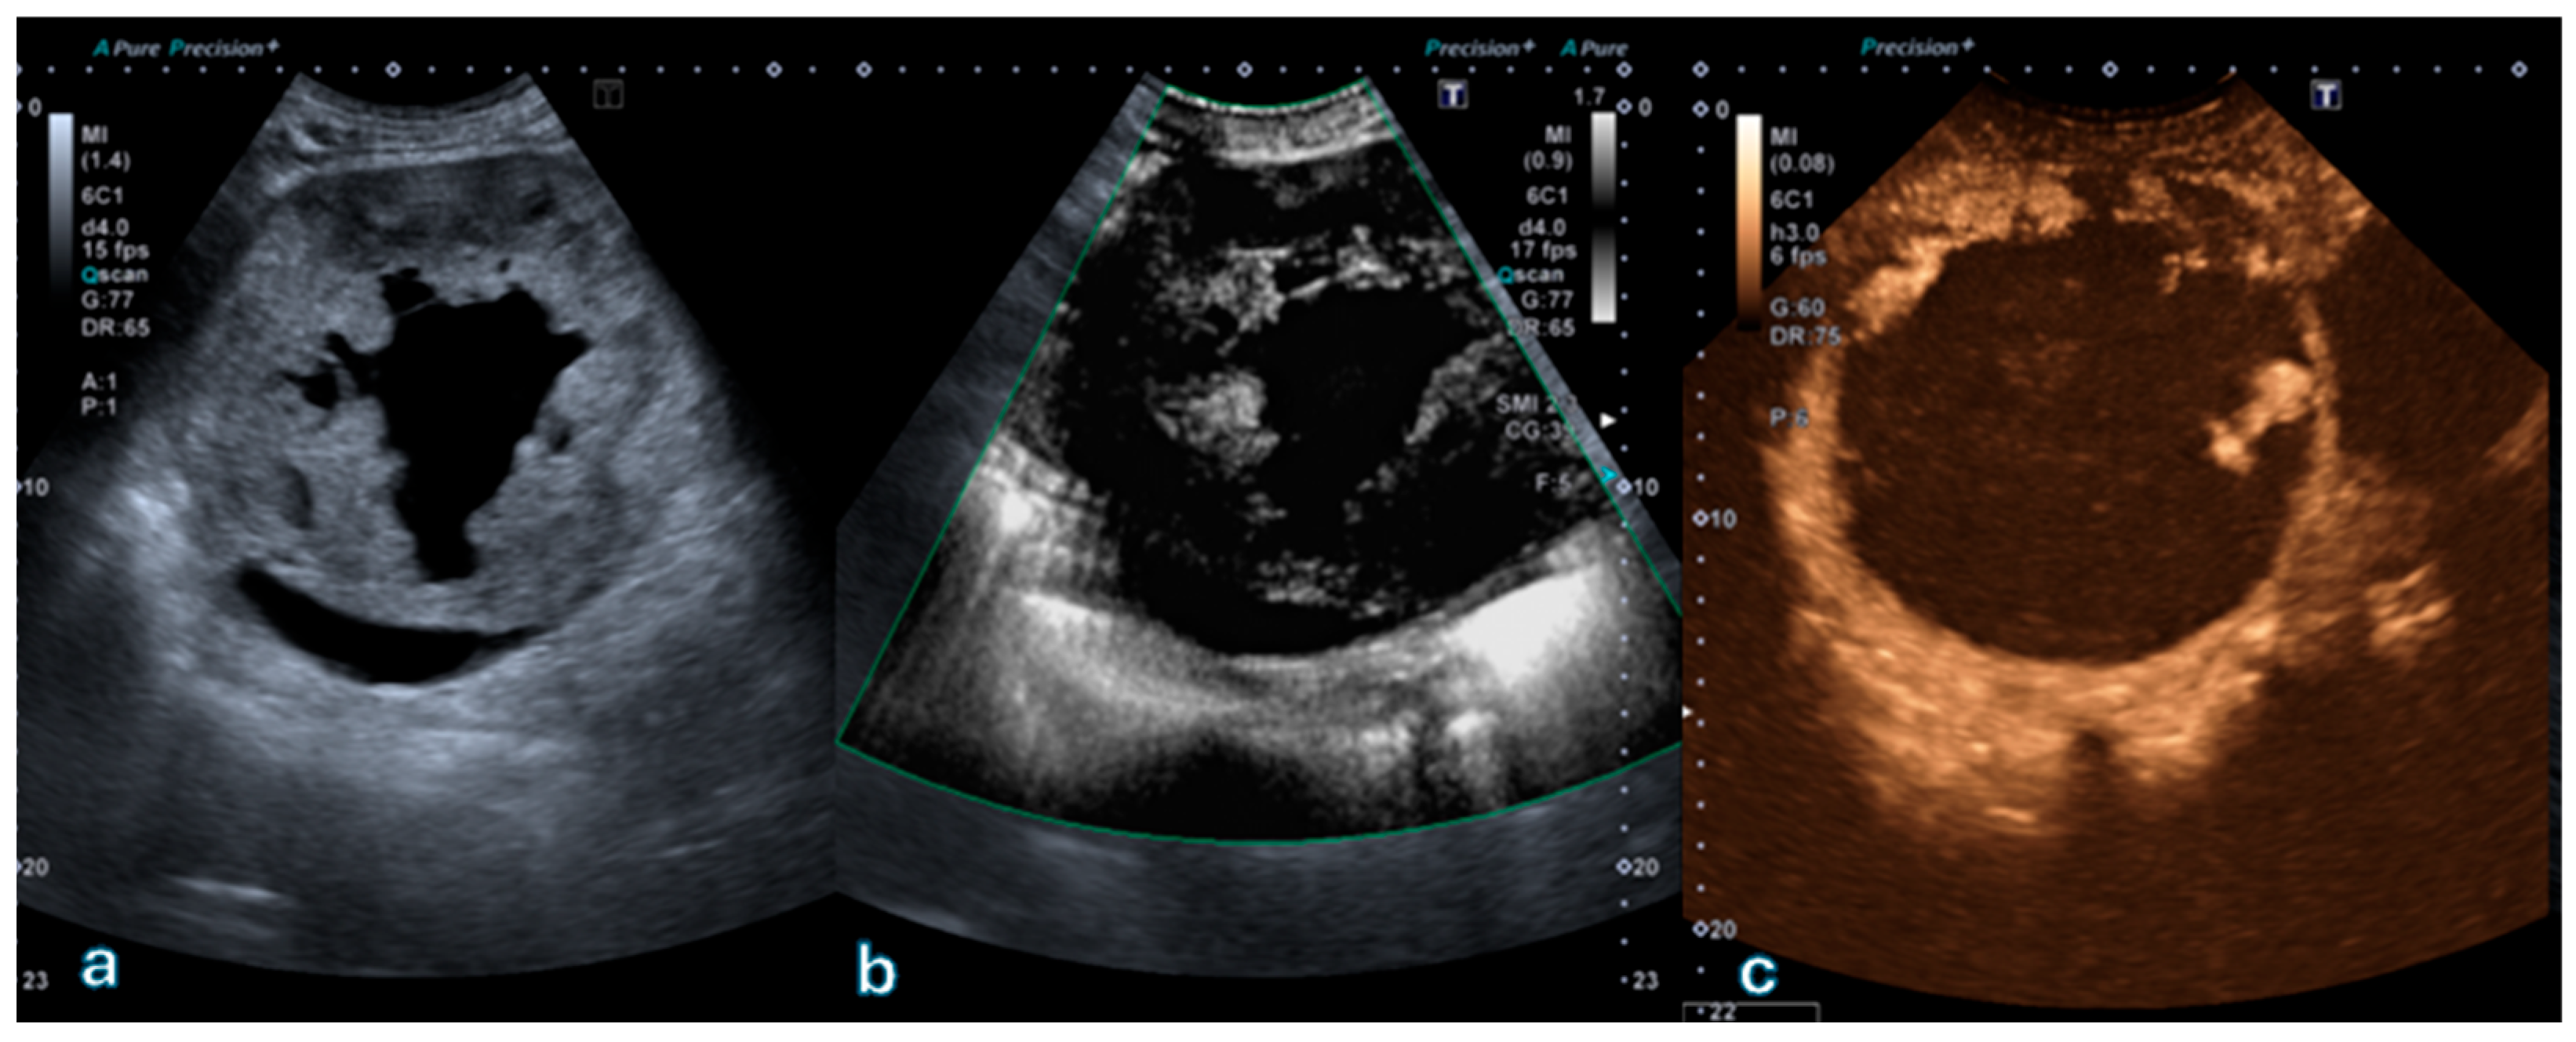

Figure 2 shows a representative case of a Bosniak II cyst with an intracystic hyperechoic component lacking vascularization on both SMI and CEUS, confirming the benign nature of the lesion.

Figure 2. Complex cystic lesion located in the upper pole of the right kidney. (a) B-mode ultrasound shows a cyst with a dependent hyperechoic intracystic component movable with changes in patient position, suggesting proteinaceous or hemorrhagic material rather than a solid nodule. (b) Superb Microvascular Imaging (SMI) demonstrates no detectable vascular signal within the hyperechoic component or cyst wall. (c) Corresponding contrast-enhanced ultrasound (CEUS) image confirms absence of enhancement, consistent with a proteinaceous cyst classified as Bosniak II. This case exemplifies concordant findings between SMI and CEUS in a Bosniak II lesion.